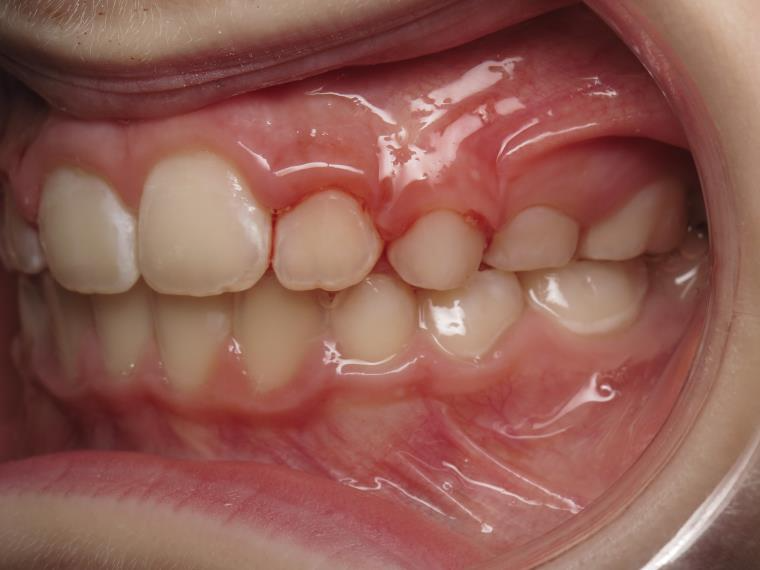

6 décalage sagittal 5 ans

Décalage entre les dents d avant en arrière